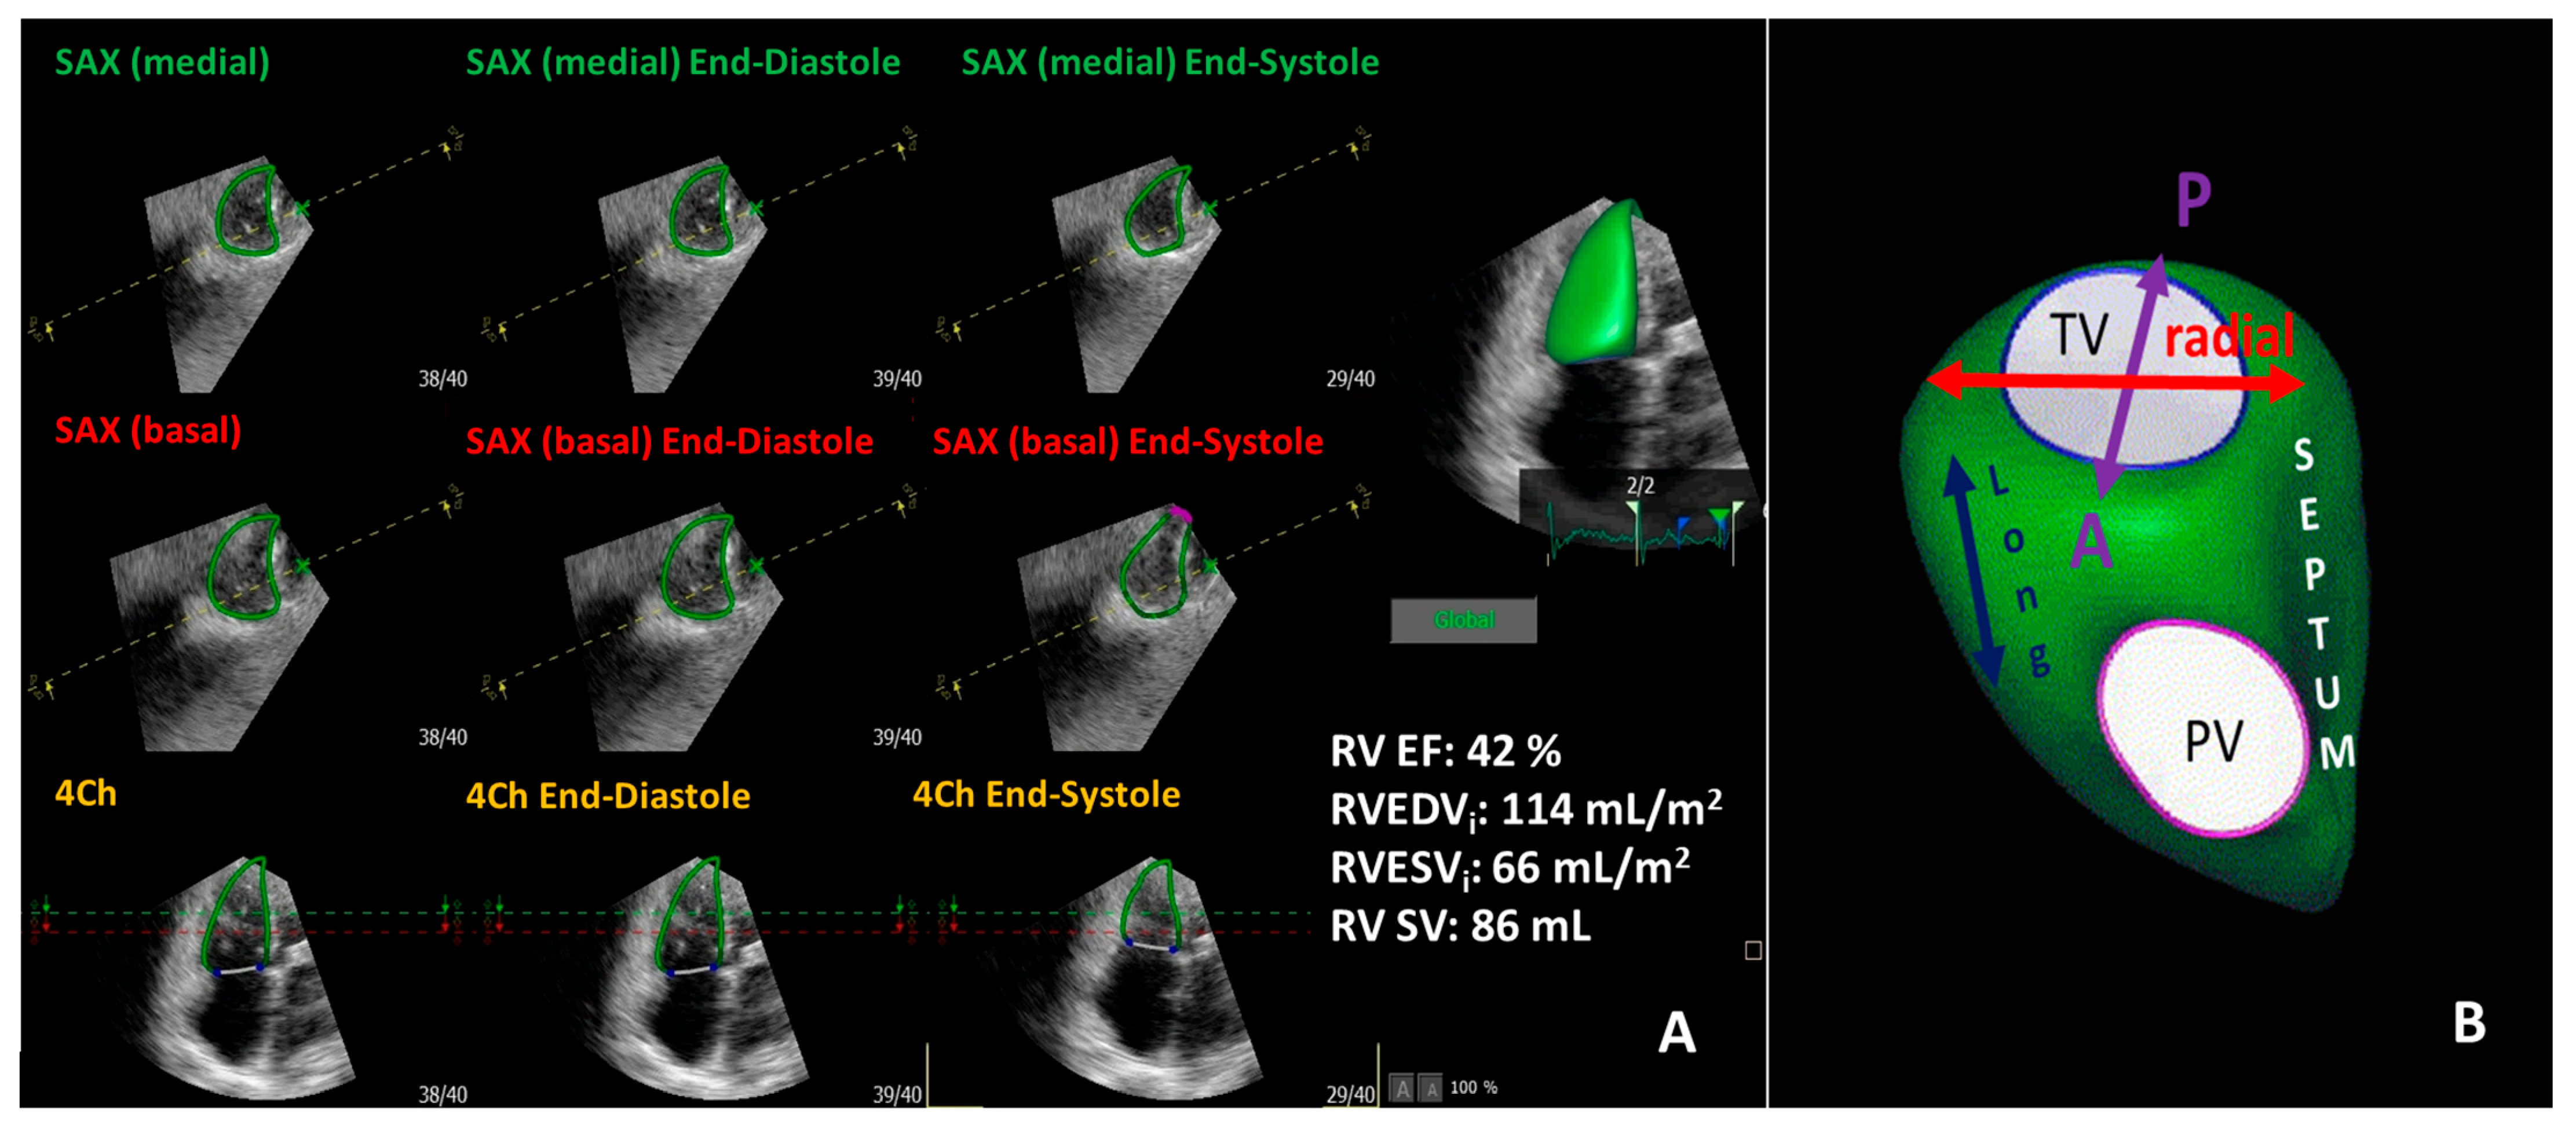

5. Three-Dimensional Echocardiography of the Right Ventricle and Tricuspid Valve

6. Added Value of 3D Echocardiography Compared to 2D Echocardiography in the Assessment of the Right Ventricle